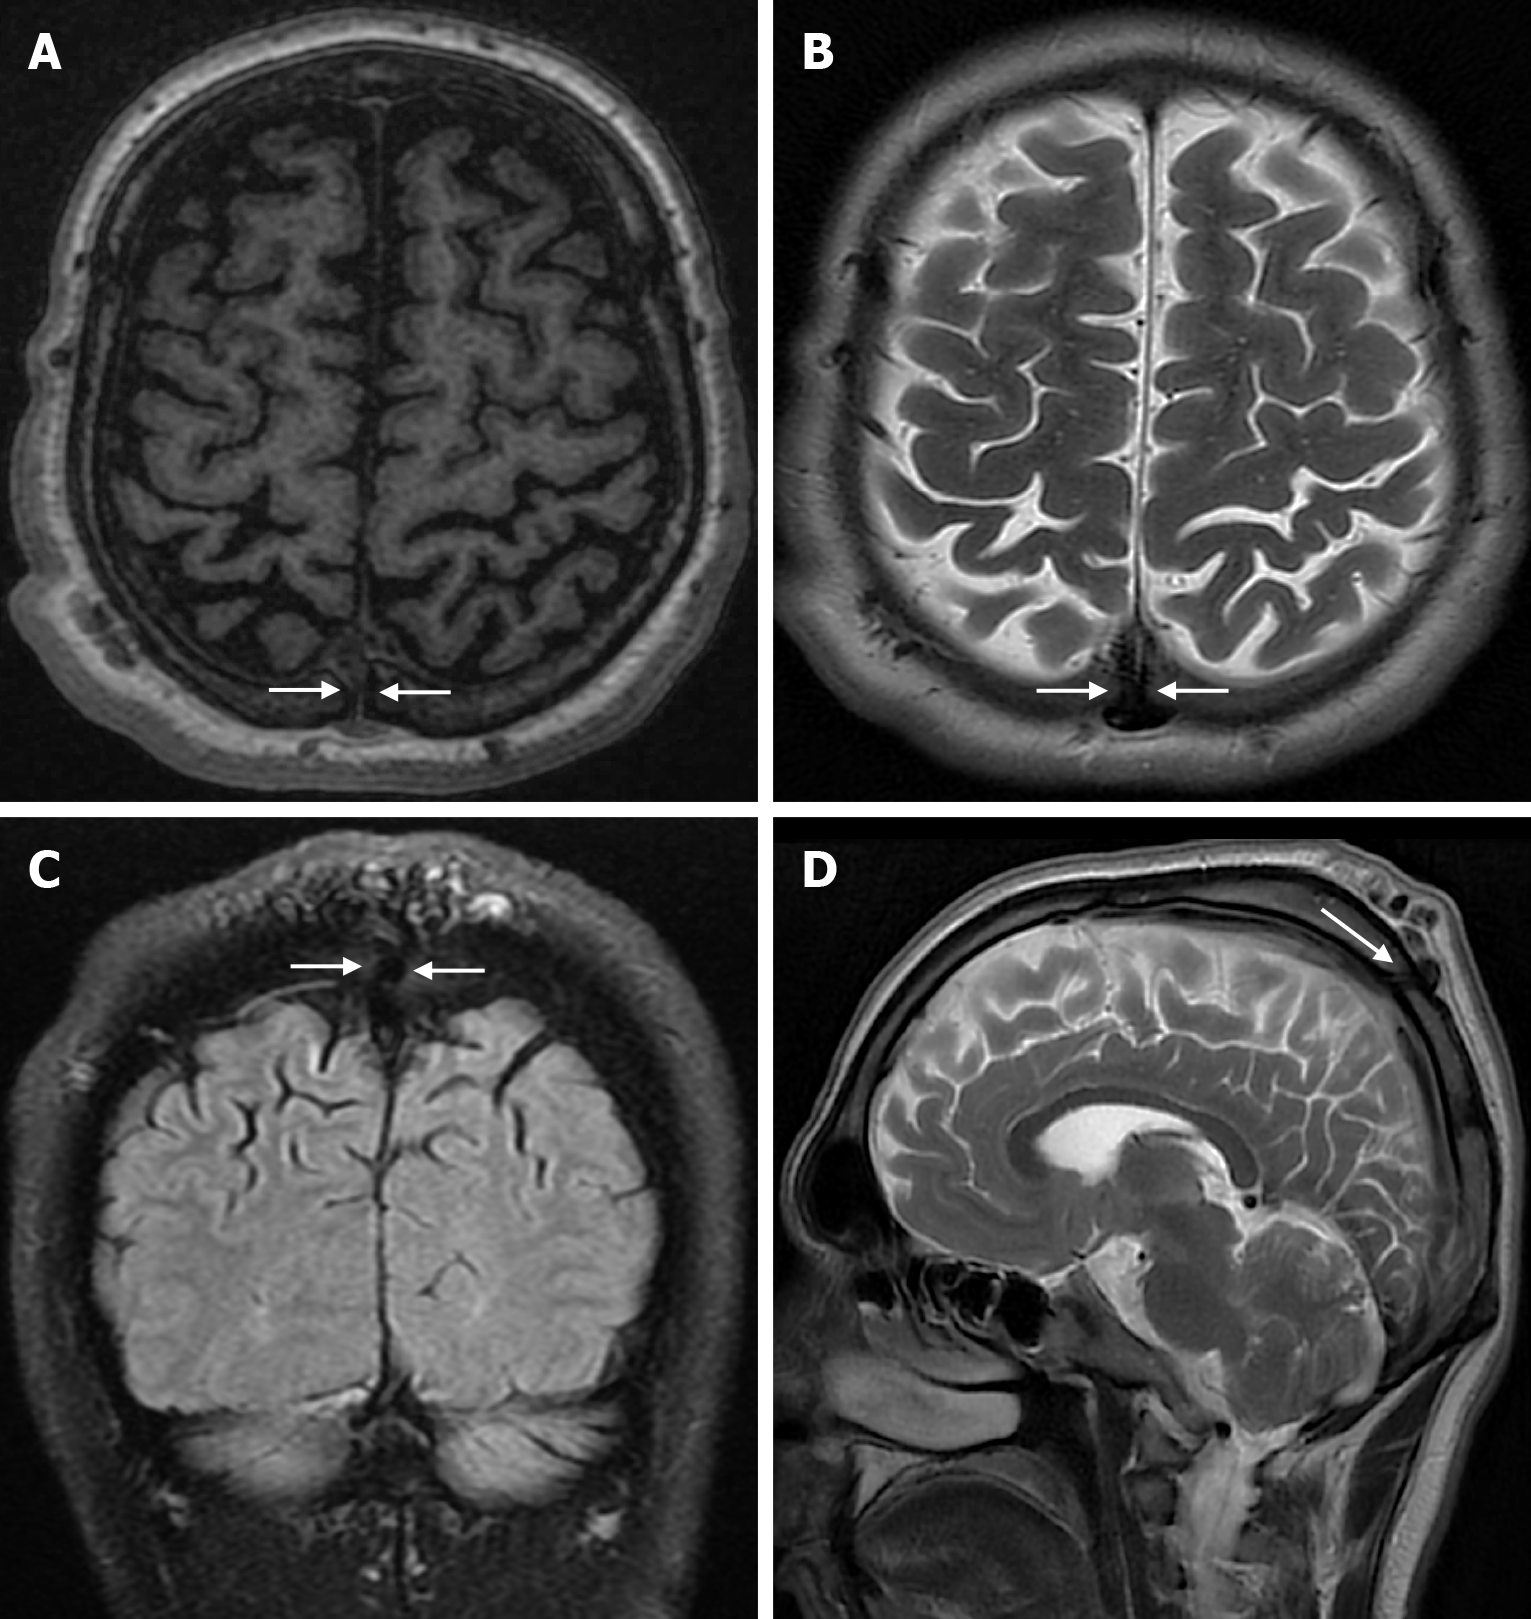

Epidermoid cysts are small or medium-sized, benign, and slow-growing tumors that arise from the remnants of ectodermal cells in the bones of the skull. These cysts can also develop after trauma or surgery. Epidermoid cysts are lined with squamous epithelium. They contain deposits of cholesterol and keratin. These cysts constitute less than 1% of primary intracranial tumours, while intradiploic epidermoid cysts account for less than 0.25% of intracranial tumours. These tumors can occur at any age from the first decade of life to the seventh decade, with a mean age of 32-38 years, and there is no gender predilection. Epidermoid cysts are most commonly found in the frontal, parietal and occipital regions and often involve more than one bone. Epidermoid cysts appear on plain radiography as round or lobulated lytic areas with smooth and sclerotic margins. On CT they appear as non-contrast enhanced intradiploic lytic hypodense lesions with smooth sclerotic borders. Epidermoid cysts often cause remodeling and widening of the inner and outer tables. Epidermoid cysts that appear hyperdense on CT due to bleeding, calcification or high protein content are called white epidermoids and are observed quite rarely. On MRI, epidermoid cysts appear isointense/hyperintense on T2-weighted and fluid-attenuated inversion recovery (FLAIR) images and slightly hyperintense on T1-weighted images (Figure 4). These lesions restrict diffusion on diffusion-weighted imaging but show no contrast enhancement on contrast enhanced sequences[19].